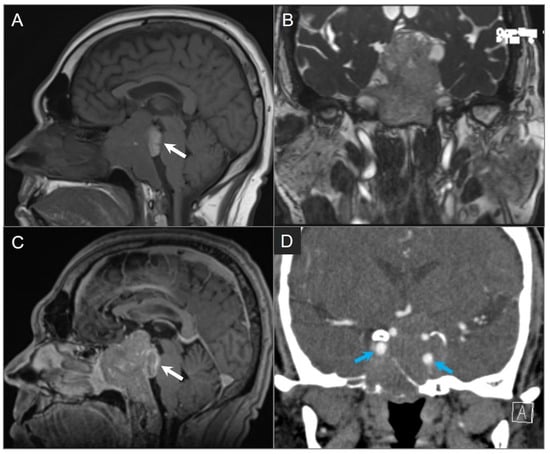

4.3.1. Intraosseous/Ectopic Pituitary Adenoma

4.3.2. Craniopharyngioma